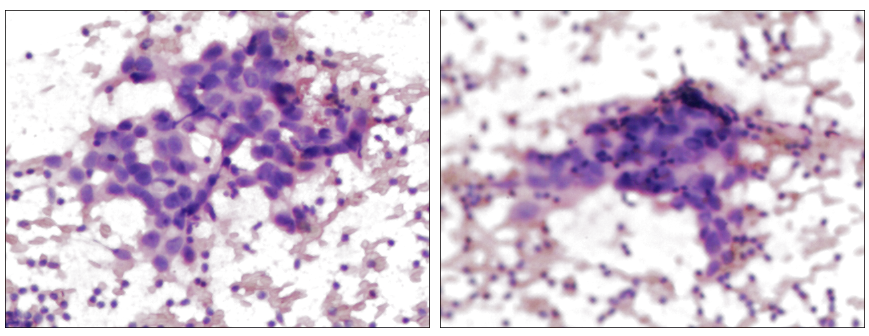

<右乳肿块>穿刺结果:浸润性癌,倾向非特殊型,Ⅱ级。免疫组化:ER(65%++),PR(70%+++),CerbB-2(3+),Ki67(40%+),AR(70%++),P53(70%弱+),SOX-10(-),CK5/6(-),P63(-),GATA-3(+),P120(膜+),E-Ca(+)。

图3.HE染色(右乳肿块)

<右腋淋巴结>超声引导下穿刺涂片:查见癌细胞,符合转移。

图4.HE染色(右腋淋巴结)